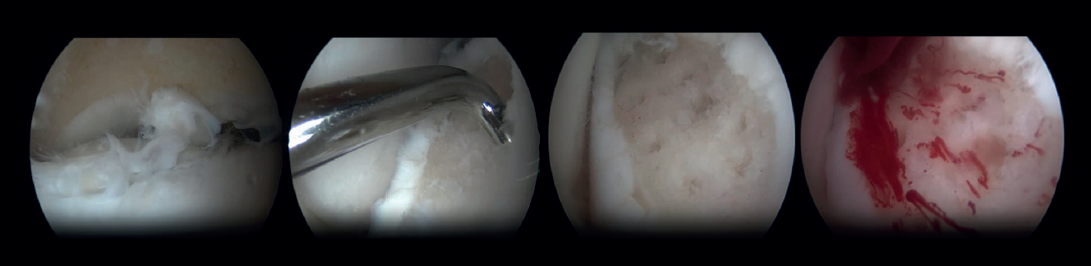

Arthroscopic Bone Marrow Stimulation (BMS) is the most frequently used treatment for primary OLT(22). BMS can be deployed for relatively smaller (<15 mm), non-cystic, non-fixable lesions(20,23). Arthroscopic BMS starts with debridement and curettage of the defective cartilage and subchondral bone(24). Subsequently, drilling or perforation of the sclerotic bone at the base of the defect is performed, often using a Kirschner wire or microfracture awl(25). The holes should be made to a depth that results in bleeding of the subchondral bone or the presence of fat droplets(23) (Figure 4). This technique disrupts the intraosseous blood vessels, leading to the subchondral bone bleeding and the formation of a fibrin clot. The release of mesenchymal blood cells promotes vascularization which induces the formation of fibrocartilage(26). When an isolated (i.e., no other damage to bone/within the joint) cartilage lesion with a macroscopically intact subchondral bone layer, is present, debridement only can be performed(27).

One specific surgical fixation technique is the Lift, Drill, Fill and Fix (LDFF) procedure(45). In this technique, the osteochondral lesion is visualized, and a beaver knife is used to create a flap. The flap is then lifted to allow for debridement and microfracturing of the subchondral bone. Cancellous bone, typically harvested from the distal tibial metaphysis, can be placed in the bed of the flap. Finally, the osteochondral flap is repositioned and fixed using bio-absorbable compression screws, chondral darts or bone pegs.

Fixation techniques have shown clinical and radiological success in 8 out of 10 patients, also maintaining their success in the long term (Figures 5 and 6). As these techniques preserve the hyaline cartilage and provide superior healing of the subchondral bone, they are advantageous over other surgical treatment options for OLTs, when feasible(39,41).